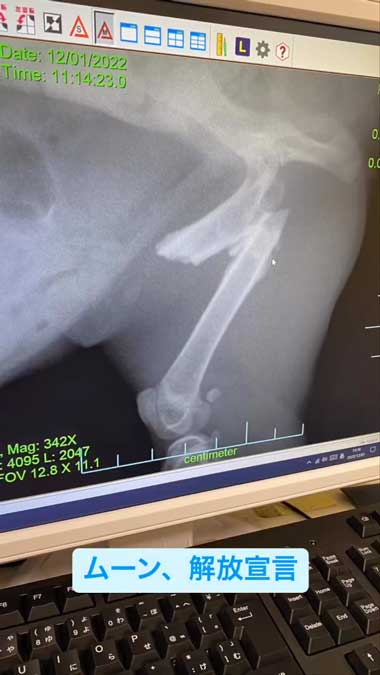

黒猫にちゅ〜るやカリカリを差し出すと、勢いよく食べはじめました。すると、「助けて」と言われた気がしたという竹岡548さん。黒猫はネットにもすんなり入ってくれたそうで、すぐにかかりつけの動物病院に。診察では黒猫は生後5〜6カ月の男の子であること、右の大腿骨(だいたいこつ)を骨折していたことが判明しました。